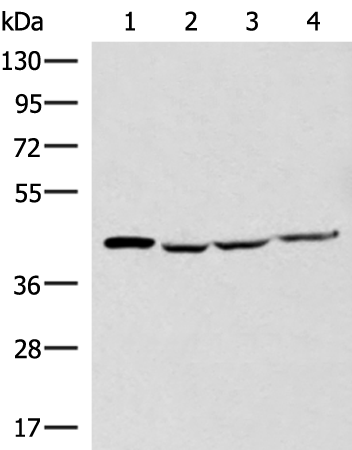

分类: 科研抗体货号: P11020别名: MCT2应用: WB,IHC反应种属: Human